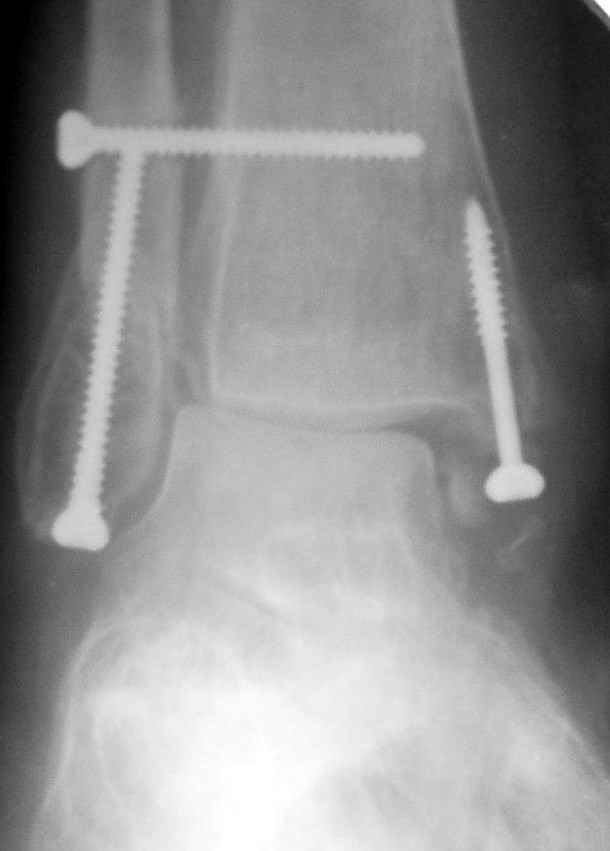

12 января прямой

12 января боковой

12 января трехчетвертной